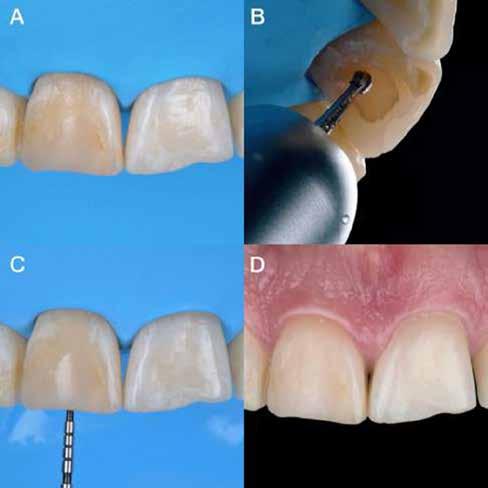

Az előzetes állapotfelmérést és a kezelés megtervezését követően a fogakat minimál invazív módon preparáltuk (1. a-b ábrák), majd az előkészített fogak ínybarázdáiba fonalbehelyező eszköz segítségével (113 Serrated Gingival Cord Packer, Hu-Friedy, Chicago, Illinois) teflonszalagot helyeztünk (Loctite Thread Seal Tape, Henkel Loctite Corp., Egyesült Államok), (1. c ábra). A hagyományos retrakciós fonalak helyett, a rugalmasságuk miatt előnyösebbnek tartjuk a teflonszalagok használatát. A kofferdámot (Dental Dam, Nic Tone, Bukarest, Románia) az előkészített fogakon kívül, az azoktól disztálisan elhelyezkedő egy-egy fognak megfelelően is perforáltuk.

Mivel a felső fogív első kisőrlőfogtól ellenoldali első kisőrlőfogig terjedő részét terveztük kerámia héjak segítségével ellátni (14-24), ezért az izolálást ugyanezen fogív második kisőrlőfogtól második kisőrlőfogig terjedő részére (15-25) helyeztük fel (2. a ábra). A kofferdám rögzítését a második kisőrlőfogakra helyezett kapcsok segítségével (Rubber Dam Clamps #2, Hu-Friedy, Chicago, Illinois, Egyesült Államok) biztosítottuk (2. b ábra). Ezt követően a gumilepedő fogakat körülvevő szélét kézi fonalbehelyező eszközzel és finom levegőáramlattal az ínybarázdákba forgattuk. A folyamat a következőképpen zajlott: a kézi eszközzel a kofferdámot a fognyaknak megfelelően finoman a szulkusz irányába fordítjuk, majd az eszköz végét a fognyaknak megfelelően vezetjük, miközben a lepedőt a puszterből jövő levegő segítsé-

A gumilepedő és a kiválasztott kapcsok (A). A kisőrlőfogakra helyezett kapcsok stabilizálják a kofferdámot (B). A gumilepedő ínybarázdákba történő beforgatása fonalbehelyező eszköz és levegőáramlat segítségével (C). Közvetlenül a héjak felhelyezése előtt a frontfogakra helyezett kapcsok (D).

ábra: A kapcsok eltávolítása és a kismetszőfogakra készült héjak beragasztása. A kapcsok nagymetszőfogakról történő eltávolítása (A). A kapcsok eltávolítása után látható állapot (B). A nagymetszőfogak és a szemfogak teflonszalaggal történő izolálása (C). A kismetszőfogak ínykapcsokkal történő kiegészítő izolálása (D). A héjak átadása után látható állapot (E).

gével finoman az ínybarázdába fordítjuk (2. c ábra). Azokra a fogakra, amelyekre aktuálisan héjakat akartunk helyezni, ezen felül kiegészítő kapcsokat is helyeztünk (Hygenic Brinker Clamp #B4, Coltene/Whaledent Inc., Cuyahoga Falls, Ohio, Egyesült Államok), (2. d ábra) Ebben a stádiumban érdemes a héjakat még bármilyen ragasztóanyag vagy próbapaszta nélkül a helyükre illeszteni (dry tryin). Erre azért volt szükség, hogy még a tényleges ragasztási folyamat megkezdése előtt ellenőrizni tudjuk a restaurátum és a fog pontos illeszkedését, valamint a széli záródási vonalhoz való akadálytalan hozzáférést (3. a ábra). Ideális esetben a héjak felhelyezését párosával, a középvonaltól disztál felé haladva végezzük. Ennek megfelelően a jobb (1.1) és bal felső nagymetszőfogakra (2.1) kapcsokat helyeztünk, majd a szomszédos fogakat teflonszalag segítségével izoláltuk. Ezt követően az 1.1-es és 2.1-es fogak héjak elhorgonyzására szolgáló felszíneit 32%os foszforsavval (Uni-Etch w/BAC, Bisco Dental, Schaumburg, Illinois, Egyesült Államok) 30 másodpercen keresztül kondicionáltuk. Ez után a felszínek vízzel történő lemosása és óvatosan

leszárítása következett (3. b ábra). A fogfelszínek előkészítésének utolsó lépéseként a primert és az adhezívet (OptiBond FL, Kerr Dental Orange, Kalifornia, Egyesült Államok) a gyártói javaslatnak megfelelően a felszínekre applikáltuk, majd 20 másodpercen keresztül polimerizációs lámpával világítottuk (Valo LED Curing Light, Ultradent Products Inc., South Jordan, Utah). Az 1.1-es és 2.1-es fogakat borító héjak ragasztása során világos színű, fényre kötő ragasztócementet (Variolink Esthetic LC, Ivoclar Vivadent, Schaan, Liechtenstein) alkalmaztunk. A ragasztóanyagot először a héjak belső felszínére vittük fel, majd ezeket az előkészített fogfelszínekre helyeztük (3. c ábra). Az approximális felszíneken megjelenő cementfelesleget egy ecset (Profi Natural Bristle Brush, Renfert, Hilzingen, Németország) és fogselyem (Oral-B Glide Pro-Health Deep Clean Floss, Procter & Gamble, Cincinnati, Ohio, Egyesült Államok) segítségével még a ragasztóanyag megvilágítása előtt eltávolítottuk. A megvilágítás során a különböző fogfelszíneket (labiális, meziális, disztális és incizális) 20-20 másodpercen keresztül világítottuk meg (3. d ábra)

Ezt követően a felső nagymetszőkre helyezett kapcsokat

egy kapocsfeszítő (4 Rubber Dam Clamp Forceps, Hu-Friedy, Chicago, Illinois, Egyesült Államok) segítségével eltávolítottuk (4. a-b ábrák). Ezután a kismetszőfogak előkészítése következett. Még a kapcsok felhelyezése előtt a szomszédos fogakat, azaz a jobb és bal felső szemfogat, valamint a felső nagymetszőfogakat (1.3, 1.1, 2.1, 2.3) teflonszalaggal izoláltuk (4.c. ábra). Ezután a korábban részletezett ragasztási protokollt követve a kismetszőfogakra készített héjakat beragasztottuk. Ezt a folyamatot a felső szemfogak, és végül az első kisőrlőfogak esetében is megismételtük (4. d-e. ábrák)